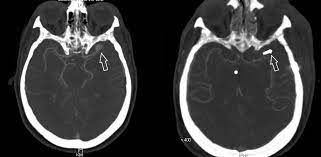

Kleines aneurysma im kopf. Ein Aneurysma vor allem im Gehirn kann angeboren sein. Häufig befinden sich die Aneurysmen im Kopf an den Aufzweigungen Bifurkationen der Arterien. Schließlich kann das Aneurysma platzen und eine unter Umständen lebensgefährliche Blutung im Kopf bewirken.

Die meisten Gefäßaussackungen im Kopf entdecken Ärzte durch Zufall oder weil sie Symptome wie beispielsweise Doppeltsehen verursachen. Bei starken Kopfschmerzen kann Fenchelsamen helfen. Gerade größere Aneurysmen können durch ihr Volumen auf angrenzende Hirn- oder Nervenstrukturen drücken.

Ein Aneurysma vor allem im Gehirn kann angeboren sein. Da das Schiff beginnt sich aufzublähen wird es wahrscheinlicher zu platzen. Niemand kann vorhersagen wann ein Aneurysma platzt und Leck Blut in die umliegenden Gebiete. Solange ein Aneurysma noch klein und intakt ist das Gefäß also keine Risse hat verursacht es häufig keinerlei oder nur unspezifische Beschwerden wie Kopfschmerzen oder Übelkeit. Wenn ein Blutgefäß erweitert oder Ballons durch Schwächung Wände heißt es ein Aneurysma. Je nach Größe und Lage des Aneurysmas im Gehirn können jedoch auch Beschwerden auftreten. Ein Aneurysma ist eine krankhafte Aussackung einer Schlagader. Fachleute gehen aber davon aus dass Aneurysmen mit einem Durchmesser unter sieben Millimetern nicht sofort behandelt werden müssen sondern beobachtet werden können. Je nach Größe und Ort sind weitere Symptome möglich.

Nicht rupturierte intrakranielle Aneurysmen finden sich bei etwa drei Prozent der Erwachsenen. Ein Aneurysma ist eine krankhafte Gefäßausstülpung also eine örtlich begrenzte Erweiterung einer Arterie. Ein Aneurysma ist eine krankhafte Gefäßausstülpung die sich an den hirnversorgenden Gefäßen zumeist an Gefäßaufzweigungen befindet. Die meisten Gefäßaussackungen im Kopf entdecken Ärzte durch Zufall oder weil sie Symptome wie beispielsweise Doppeltsehen verursachen. Täglich im Kühlschrank aufbewahren. Aber es lässt sich nicht ganz ausschließen dass auch solche kleinen Aneurysmen reißen. Niemand kann vorhersagen wann ein Aneurysma platzt und Leck Blut in die umliegenden Gebiete.